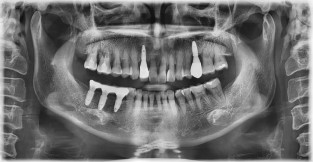

전체어금니

치료기간 : 2022-03-05 ~ 2022-10-01

1. 상기 x-ray 이미지 모두 동일한 해당 의료기관에서 진료한 환자입니다.

2. 상기 x-ray 이미지 모두 동일 인물의 것입니다.

3. 치료 전 이미지는 2022-03-05에 촬영했으며, 치료 후 이미지는 2022-10-01에 촬영하였습니다.

4. 상기 x-ray 이미지 모두 동일 조건에서 환자분의 동의를 받아촬영되었습니다.

* 임플란트 시술은 환자분의 상태(고혈압, 당뇨 등)에 따라 부작용이 있을 수 있으니, 반드시 전문의와 상담이 필요합니다.

* 임플란트 수술 부작용

: 수술 후 출혈, 교합, 통증, 붓기, 염증 등의 문제점이 발생할 수 있습니다.)